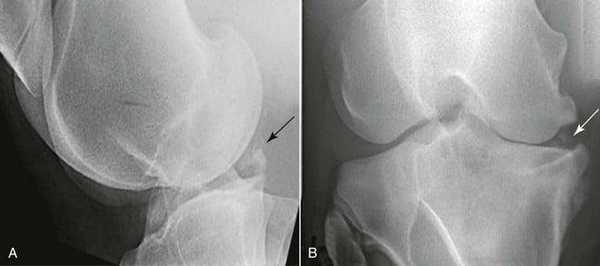

- Рентгенография коленного сустава. Не позволяет оценить состояние хрящевой ткани. Назначается для исключения других патологий и выявления сопутствующих изменений костных структур: расширения суставной щели, уплощения суставных поверхностей бедренной и большеберцовой кости на стороне поражения.

- МРТ коленного сустава. Является золотым стандартом при данной патологии. Подтверждает повышенную толщину мениска, нарушение соотношений между максимальным диаметром и шириной рогов, изменение соотношений между шириной мениска и тибиального плато.

- Артроскопия коленного сустава. Назначается при неоднозначных результатах МРТ или на этапе подготовки к хирургическому вмешательству. Выявляет необычно большую площадь мениска, при травматических повреждениях обнаруживает разрывы.